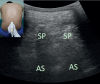

Ultrasonography has gained popularity in recent years among anaesthesiologists and being used widely for regional blocks and central venous catheterization. Ultrasonography for neuraxial blocks was found beneficial especially for determining the correct needle insertion site and estimating the needle insertion depth of epidural space. In many recent studies, ultrasound guided epidural and spinal blocks have been evaluated among obstetric patients. Pre-procedural lumbar ultrasonography and real time ultrasound guidance for neuraxial blocks was the subject of these studies. We aimed to evaluate lumbar ultrasonography for obstetric neuraxial blocks. We describe the principles of lumbar ultrasound scanning techniques and present a practical review of lumbar sonoanatomy. We discuss the potential impact and benefits of the ultrasound-guided technique in improving obstetric neuraxial blocks and limitations of its use in clinical practice, based on previous studies.